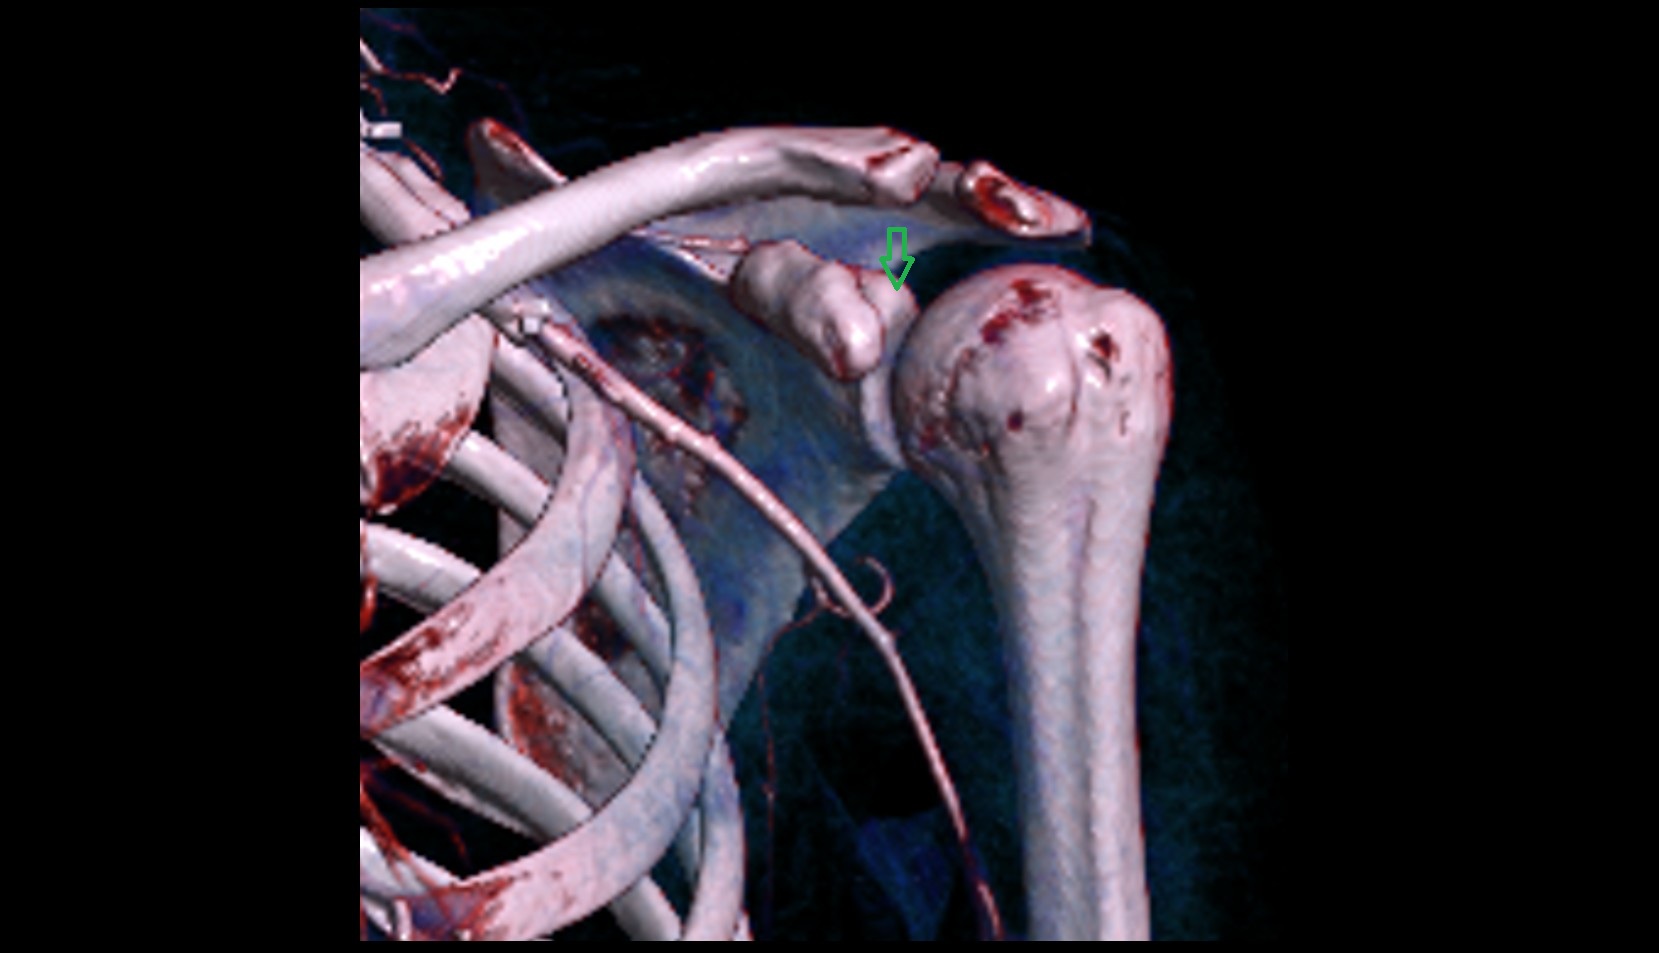

- Glenoid fossa

- Glenoid process of scapula

- Spine of scapula

- Acromion process of scapula

- Coracoid process of scapula

- Scapular body

- Neck of scapula

- Humerus

- Head of humerus

- Shoulder joint (glenohumeral joint)

- Acromioclavicular joint